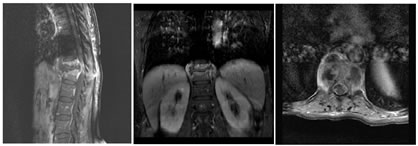

A; SAGITTAL T1W; B: SAGITTAL T2W; C: CORONAL T1 CONTRAST FAT SAT

D: SAGITTAL T1 CONTRAST FAT SAT; E: AXIAL T1CONTRAST FAT SAT

Figure 5: 47 year old male k/c/o TB presenting with low grade backache for 2 months. T12 vertebra collapse with partial destruction of anterior aspects of the T9- T11 and L1 vertebrae (A,B). Kyphotic deformity is seen at T12 level. Large abcess seen in prevertebral, intravertebral, paraspinal and epidural region seen extending from the T9 -L1 level also invloving left psoas muscle. Spinal canal stenosis and cord compression seen.